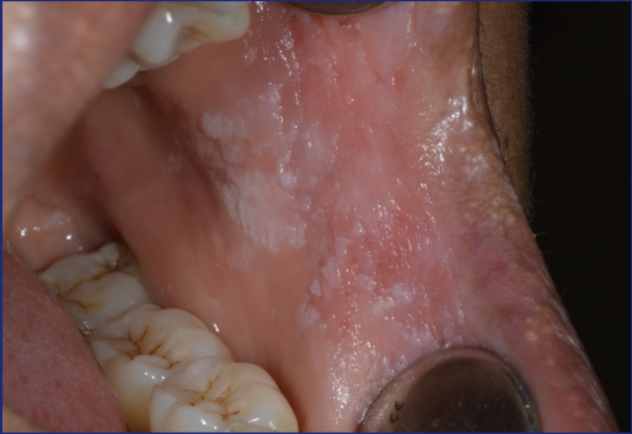

Fibro-epithelial polyp

What is this?

Fibro epithelial polyp

Usually caused by trauma and can be very common, it is slow growing and painless - usually removed because of irritation